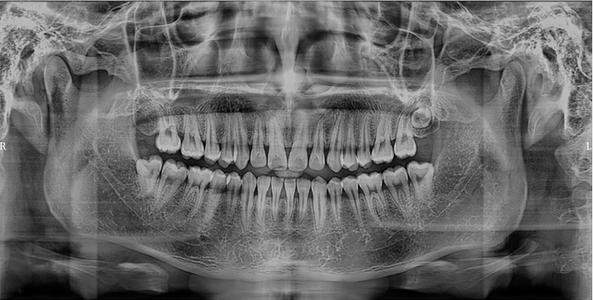

当然,还有一些问题无法通过肉眼看到,医生会建议你拍张片子,观察牙齿的深度问题,比如这样的:

长这个样子,应该不便宜吧?其实不是。这种全景片大概几十块钱,而且可以拿回来反复使用,不用担心换家医院不能用,不会的,所以这也算是省了一笔钱。